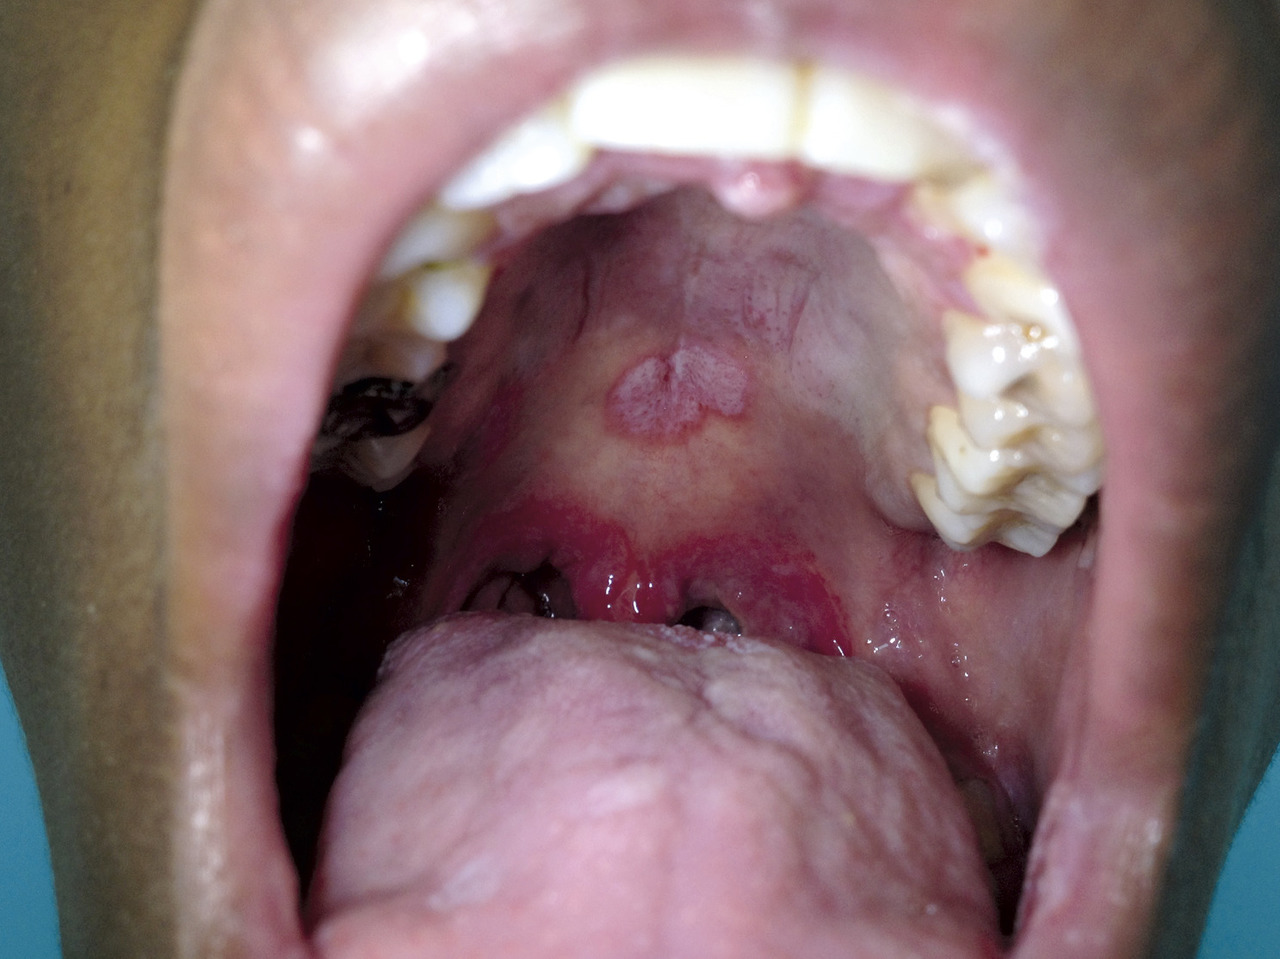

Une atteinte muqueuse (fig. 14-16) est fréquente (plaques muqueuses contagieuses génito-anales et buccales). Une alopécie dite en clairière peut également survenir (fig. 17, 18).

Les autres manifestations sont contingentes : fébricule, poly­adénopathies, arthrites, ostéite, hépatite, glomérulonéphrite uvéite, méningite (et atteinte des paires crâniennes) constituant autant de diagnostics différentiels trompeurs. Les atteintes ophtalmologiques et neurologiques peuvent engager le pronostic fonctionnel (surdité, troubles visuels).